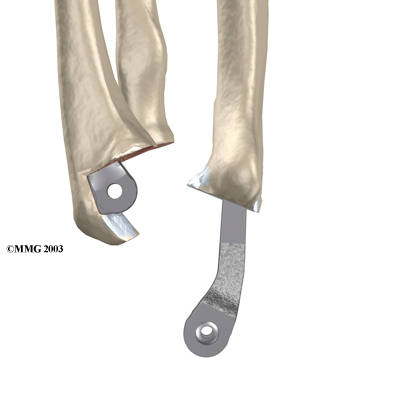

Each prosthesis has two parts. The humeral component replaces the lower end of the humerus in the upper arm. The humeral component has a long stem that anchors it into the hollow center of the humerus. The ulnar component replaces the upper end of the ulna in the lower arm. The ulnar component has a shorter metal stem that anchors it into the hollow center of the ulna.

The hinge between the two components is made of metal and plastic. The plastic part of the hinge is tough and slick. It allows the two pieces of the new joint to glide easily against each other as you move your elbow. The hinge allows the elbow to bend and straighten smoothly.

There are two different ways to hold the artificial elbow in place. A uses a special type of epoxy cement to glue it to the bone. The has a fine mesh of holes on the surface. Over time, the bone grows into the mesh, anchoring the prosthesis to the bone.

Once the joint is exposed, the first step is to remove the joint surfaces of the ulna and the radius. This is usually done with a surgical saw. The surgeon then uses a special rasp to hollow out the marrow space within the ulna to hold the metal stem of the ulnar component. The ulnar component is then to test the fit. If necessary, the surgeon will use the rasp to reshape the hole in the ulna.

When the ulnar component has been fitted correctly, the surgeon repeats the procedure on the .

After the humeral component has been fitted, the surgeon puts together the pieces of the implant and checks to see if the hinge is working correctly. The implant is then removed, and the bone is prepared to cement it in place. The pieces are cemented in place and put together. After another check for proper fit and motion, the surgeon sews up the incision.